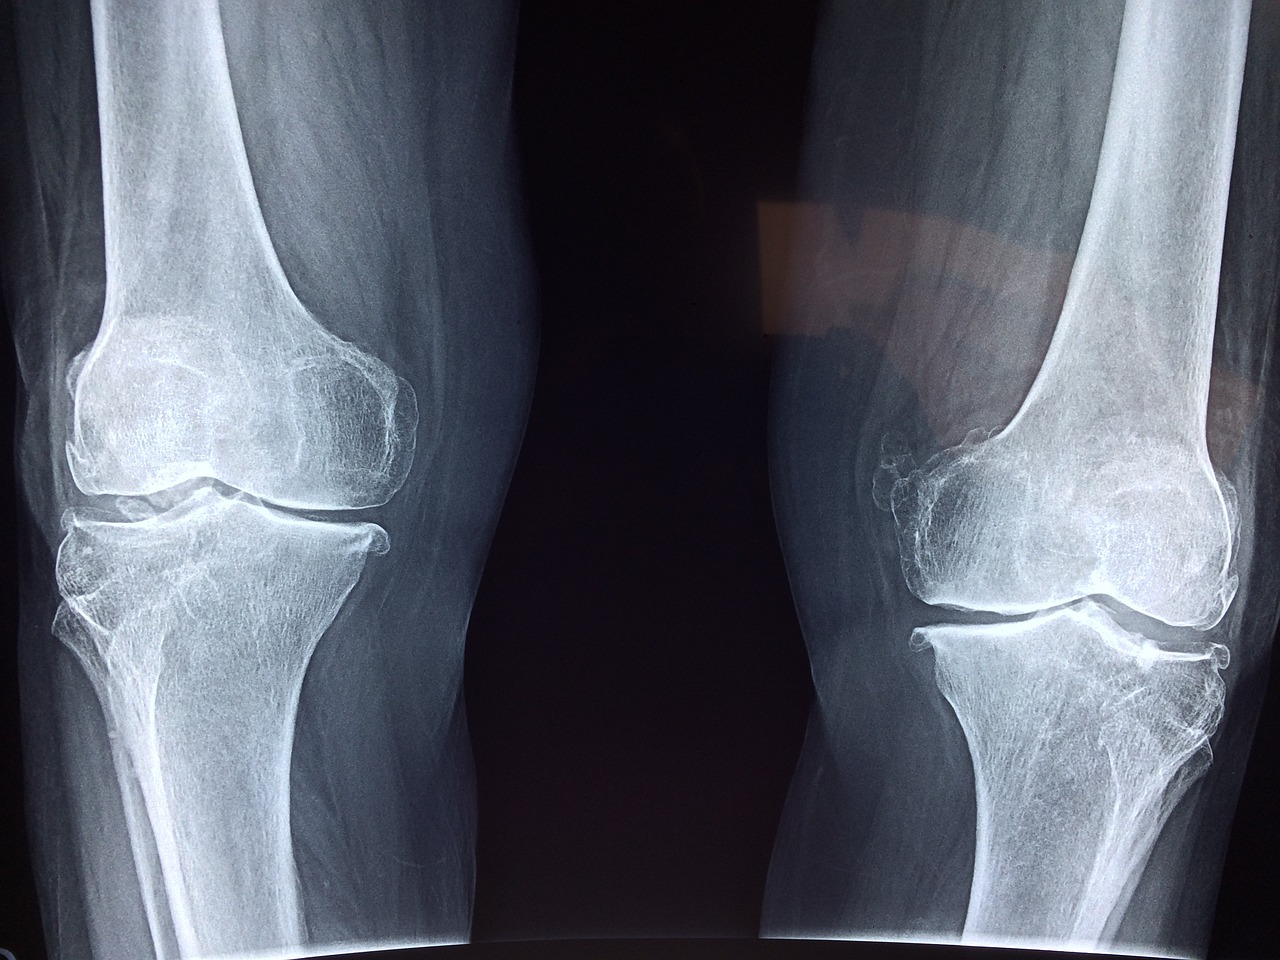

2025년 현재, 무릎 질환으로 고통받는 노인 인구가 꾸준히 증가하고 있습니다. 특히 퇴행성 관절염으로 인한 수술이 필요한 노인들에게 무릎인공관절 수술 지원사업은 매우 유용한 복지 제도입니다.

정부는 퇴행성 무릎 관절염 등으로 고통받는 저소득 노인층에게 무릎인공관절 수술비를 지원하는 제도를 운영해오고 있습니다. 이 사업은 노인들의 삶의 질을 올리고, 경제적 부담을 줄이기 위한 복지 정책의 하나입니다.

- 무릎에 인공관절치환술이 필요하다는 진단을 받은 노인